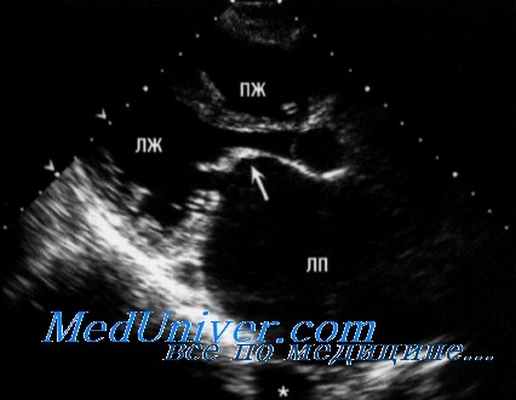

Эхокардиография при митральном стенозе

Причиной стеноза митрального клапана обычно является ревматизм. Редко стеноз МК может быть врожденным, связанным с дегенеративной кальцификацией, гиперэозипофилией, инфекционным эндокардитом, влиянием радиации и лекарственных препаратов. Типичные признаки ревматического стеноза МК можно обнаружить при ЭхоКГ в М- и В-режимах. Площадь отверстия МК измеряют планиметрически в парастернальной позиции по короткой оси. Трехмерная ЭхоКГ позволяет лучше определить площадь отверстия клапана у больных со стенозом МК или у перенесших комиссуротомию.